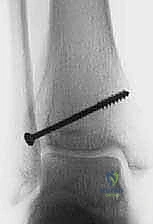

- كسر تيلوكس للمراهقين (Juvenile Tillaux Fracture): هو كسر من النوع الثالث لسالتر-هاريس، يحدث في الجزء الأمامي الوحشي (الخارجي) من قصبة الساق. يحدث عندما يكون الجزء الإنسي من لوح النمو قد أغلق، بينما الجزء الوحشي لا يزال مفتوحًا، فيقوم الرباط (AITFL) بانتزاع هذه القطعة.

- الكسر ثلاثي المستويات (Triplane Fracture): كسر شديد التعقيد يمر عبر ثلاثة مستويات مختلفة (سهمي، إكليلي، وعرضي). يظهر في الأشعة الأمامية ككسر سالتر-هاريس من النوع الثالث، وفي الأشعة الجانبية ككسر من النوع الثاني. يتطلب هذا الكسر دائمًا فحصًا مقطعيًا (CT Scan) لتقييمه بشكل صحيح.

- الأشعة السينية (X-rays): هي الخطوة الأولى والأساسية. يتم التقاط صور من زوايا متعددة (أمامية، جانبية، ومائلة) لتقييم الكسر.

- الأشعة المقطعية ثلاثية الأبعاد (3D CT Scan): تُعد ضرورة حتمية في حالات كسور تيلوكس والكسور ثلاثية المستويات، أو أي كسر يمتد داخل المفصل. توفر الأشعة المقطعية خريطة دقيقة لحجم القطع العظمية ومقدار التباعد (Displacement)، مما يساعد في التخطيط الجراحي المسبق.

ثانياً: التدخل الجراحي (الرد المفتوح والتثبيت الداخلي - ORIF)

* جميع كسور سالتر-هاريس من النوع الثالث والرابع إذا كان هناك تباعد أكثر من 2 ملم في السطح المفصلي.

* كسور تيلوكس والكسور ثلاثية المستويات ذات الانزياح الواضح.